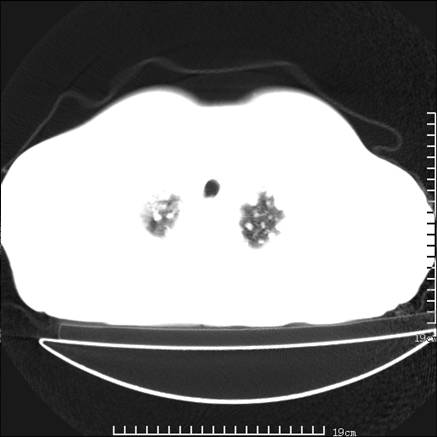

张男,75岁,干咳半年余,小便不利二年,b超检查前列腺增大,未见明显肿块;前列腺癌血生化检查多项指标明显增高。

双肺内多发转移瘤,纵膈淋巴结转移。来源前列腺?建议盆腔mri进一步检查。

双肺转移满了。

两肺广泛转移瘤。